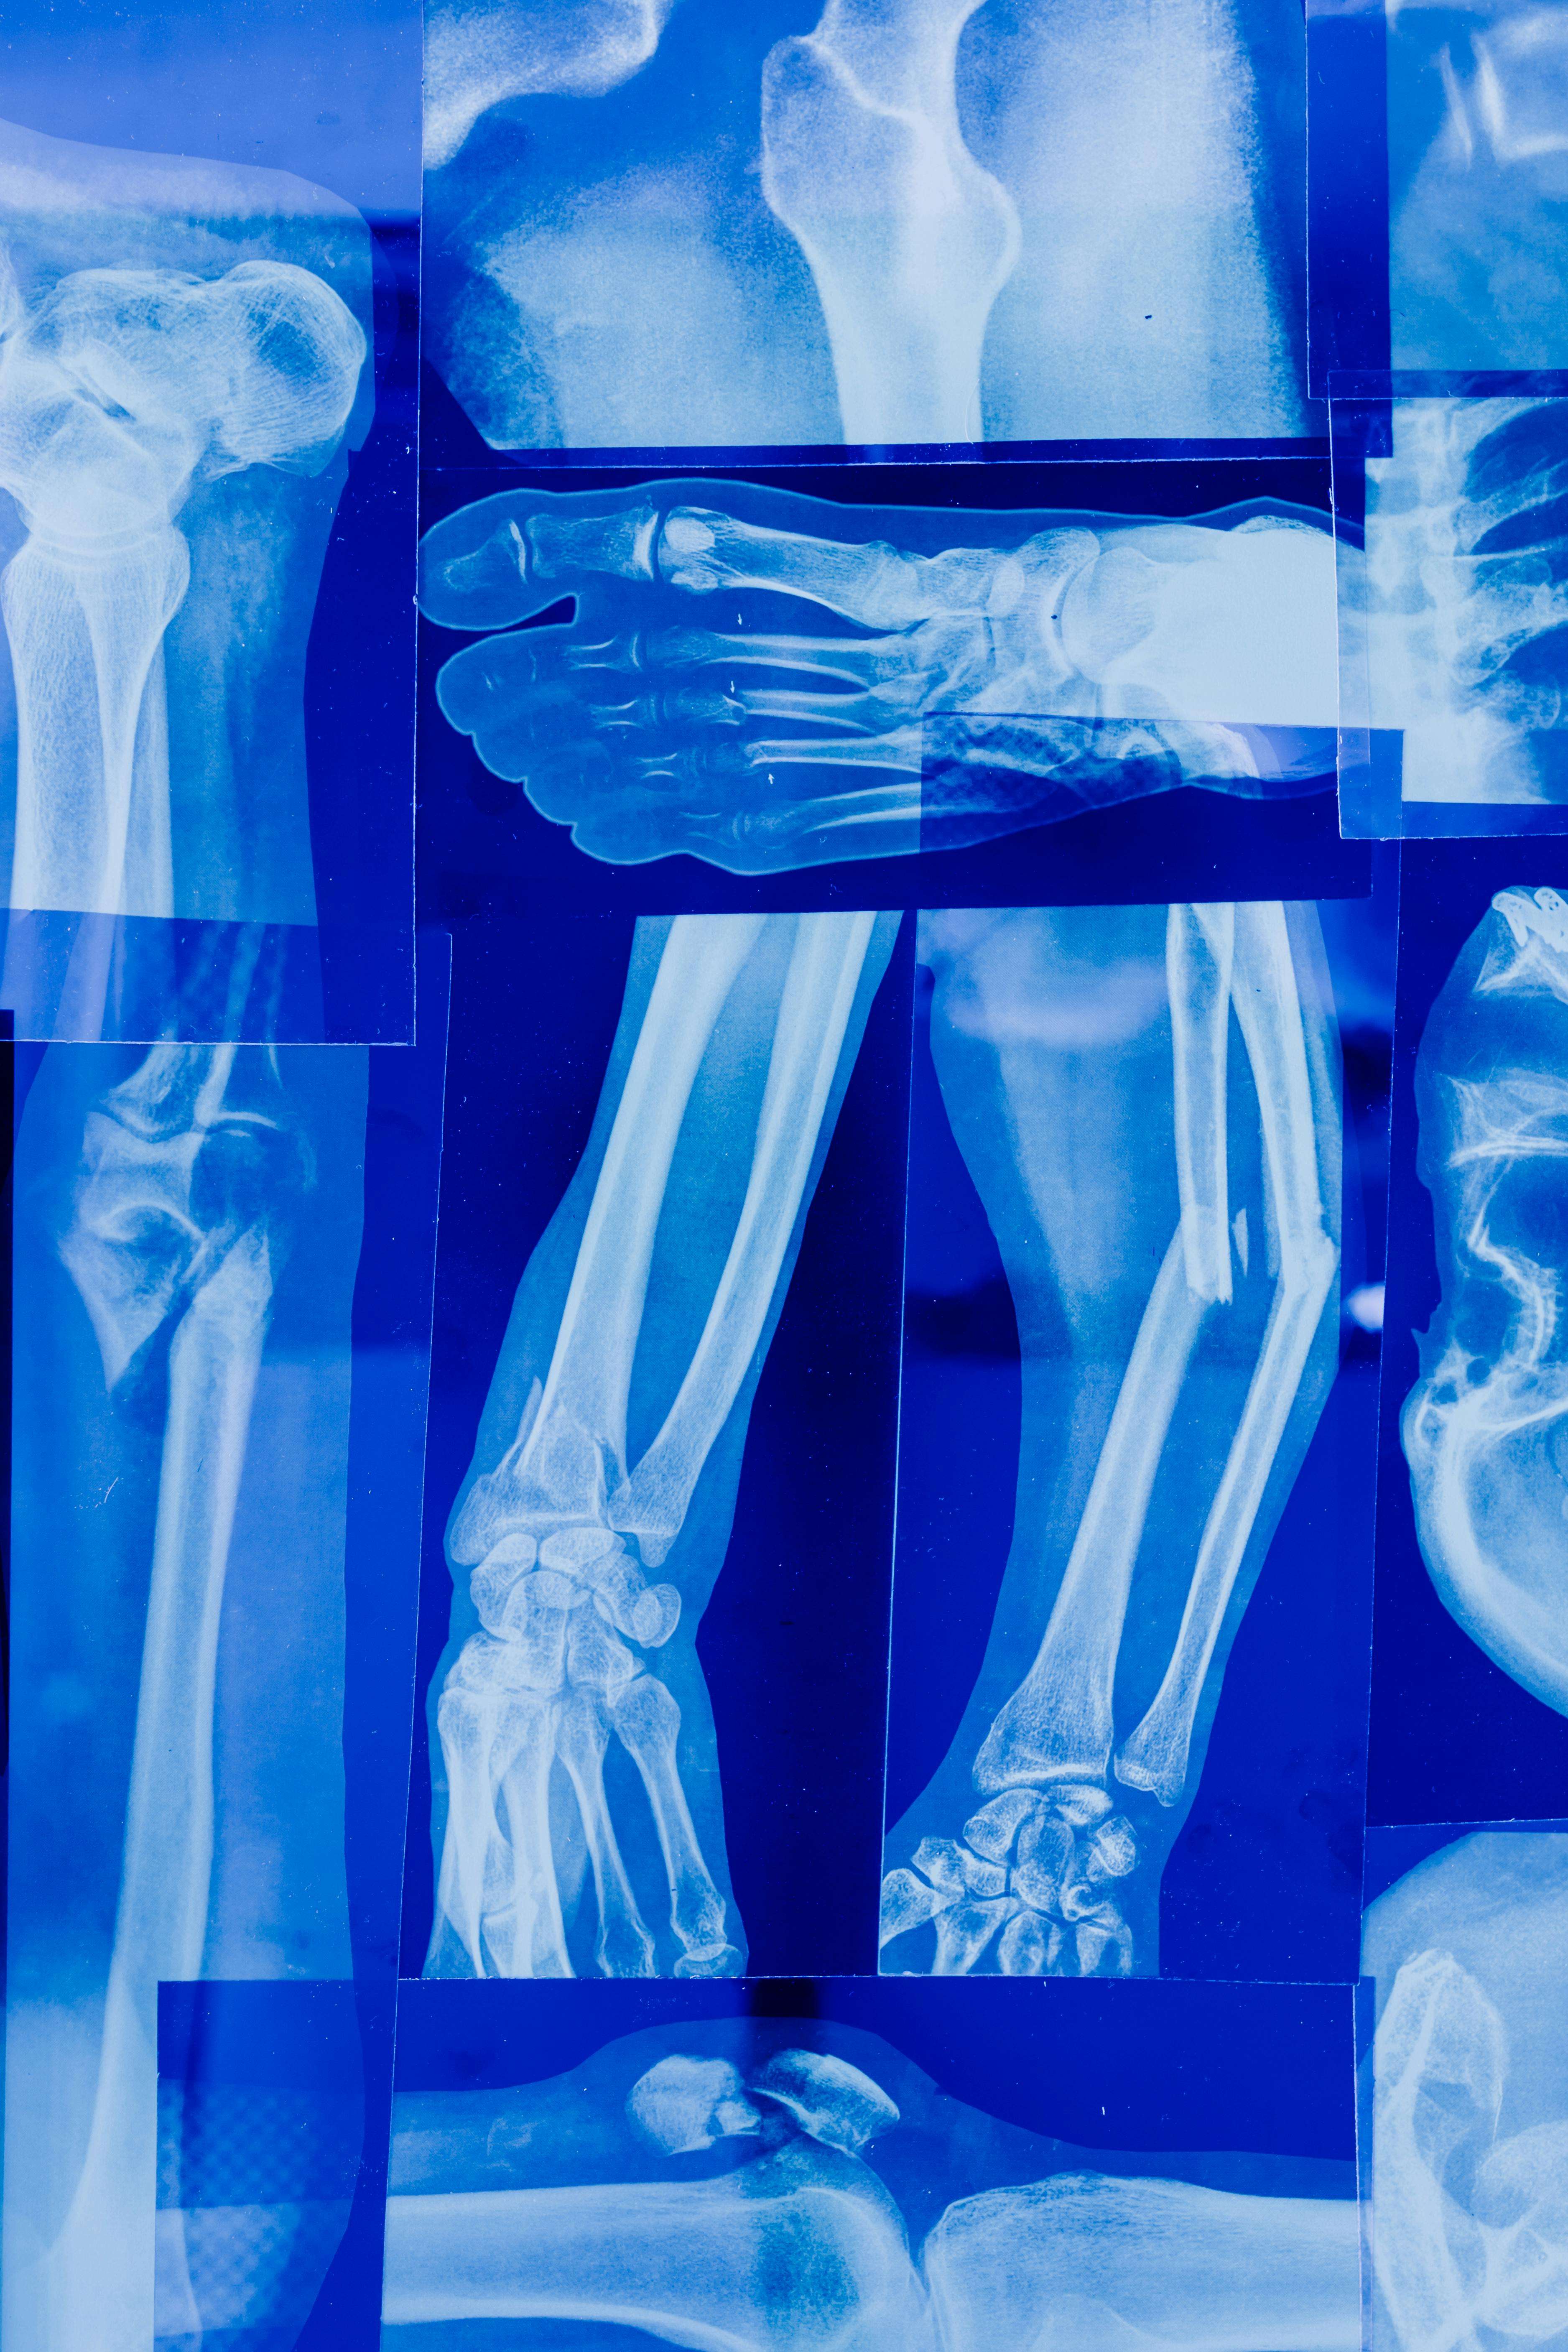

عادةً ما يتضمن تشخيص إصابة أربطة الركبة الفحص البدني والتاريخ الطبي واختبارات التصوير مثل الأشعة السينية أو التصوير بالرنين المغناطيسي أو الأشعة المقطعية. يعتمد علاج إصابة أربطة الركبة على شدة الإصابة وموقع الإصابة والصحة العامة للفرد. يمكن علاج الإصابات الخفيفة بالراحة والثلج والضغط والارتفاع (RICE)، بالإضافة إلى العلاج الطبيعي لتحسين القوة والمرونة. قد تتطلب الإصابات الأكثر خطورة التدخل الجراحي، مثل إعادة بناء أو إصلاح الرباط المصاب.